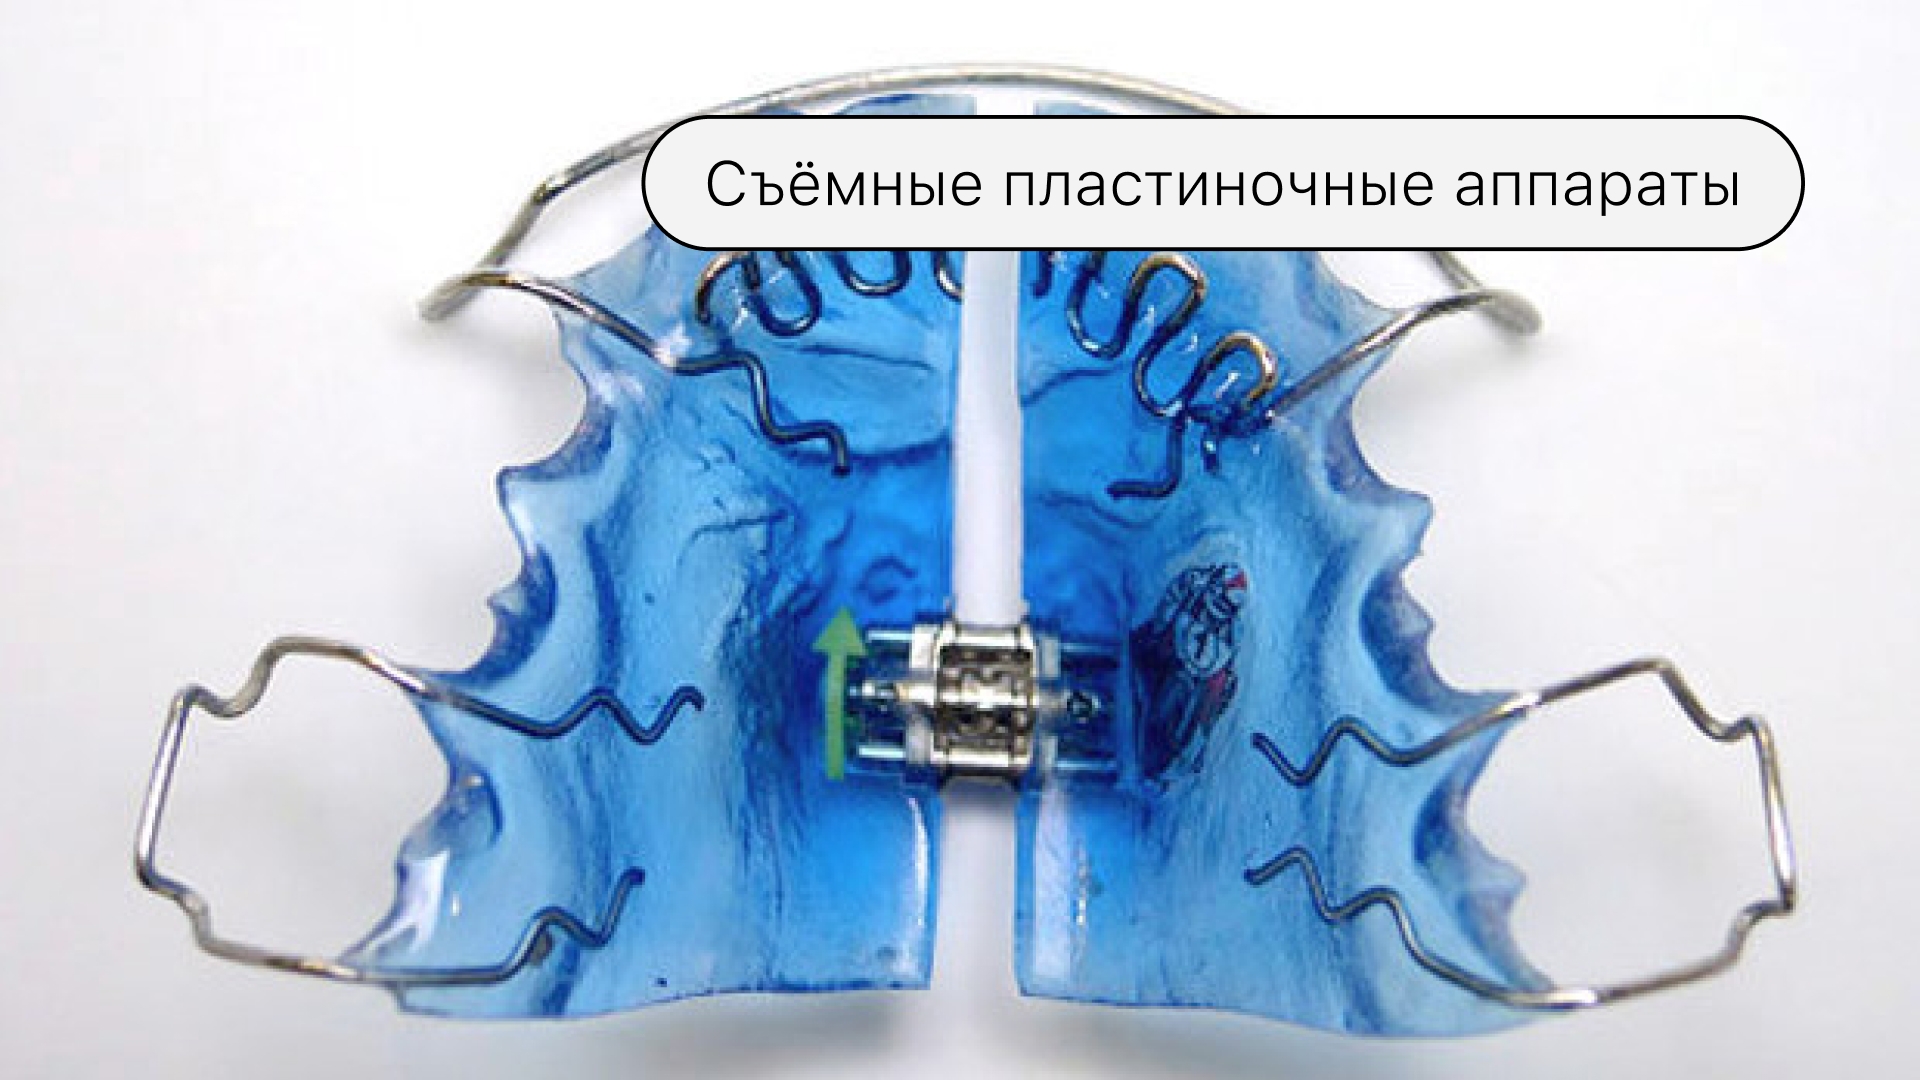

Съёмные пластиночные аппар�аты

Данные конструкции можно использовать только до 12 лет. С помощью таких приспособлений можно скорректировать размер челюстей, их форму, и подготовить зубные ряды к следующему этапу лечения.